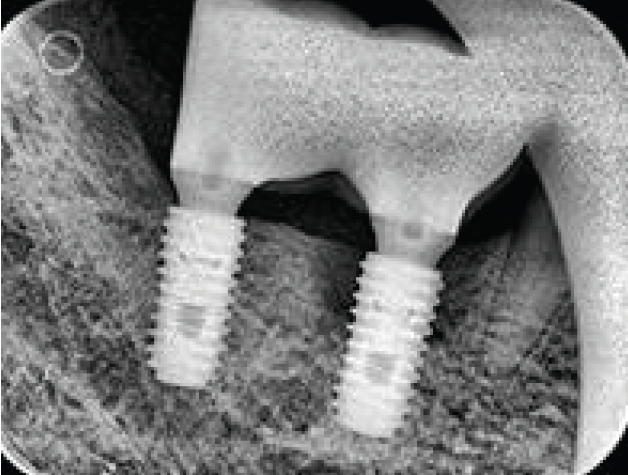

임플란트는 많이 심을수록 확률적으로 실패도 늘어나고 이에 따라 임플란트를 제거해야 하는 경우도 늘어나게 되었다. 2014년 7월 1일 임플란트 제거와 관련된 고시가 새로 발표된 이후로는 단순과 복잡으로 정리되었다. 단순 임플란트제거술은 임플란트 동요도가 있는 경우로 정의되어 구강내 식립 위치에 무관하게 적용되고 있다. 반면에 복잡 임프란트제거술은 동요도가 없는 경우에 임플란트 주위염, 파절 신경손상 등에 적용되는데 trephine bur 또는 별도의 제거 전용 키트를 사용하는 경우에 적용된다. 따라서 버를 사용하지 않더라도 라쳇(rachet)이나 토커렌치(torque rench) 등으로 제거하는 경우에도 적용 가능하다.

주의해야 하는 사항은 trephine bur를 사용하고서는 별도의 비용을 추가로 청구하는 것은 허용되지 않는다는 것이다(Fig. 2), trephine bur를 처음 사용하는 경우 주의해야 하는 것은 적용 시에 역회전으로 방향을 먼저 잡은 이후 정방향으로 바꿔서 제거해야 한다는 것이다. 임플란트 보다 사이즈가 큰 것을 사용해야 하는데 시판되는 trephine bur는 내경과 외경이 보통 1mm의 차이를 보인다. 따라서 4mm 직경의 임플란트를 제거하기 위해서는 내경이 4mm 이상 이어야 히고 외경은 5mm 이상이 된다 그러나 현실적으로는 내경이 5mm이상인 것을 적용해야 제거가 쉬우므로 제거 후 결손부가 굉장히 광대하게 발생 된다.

Fig. 2.

Trephine bur로 임플란트제거

jkda-2026-64-2-006f2.jpg